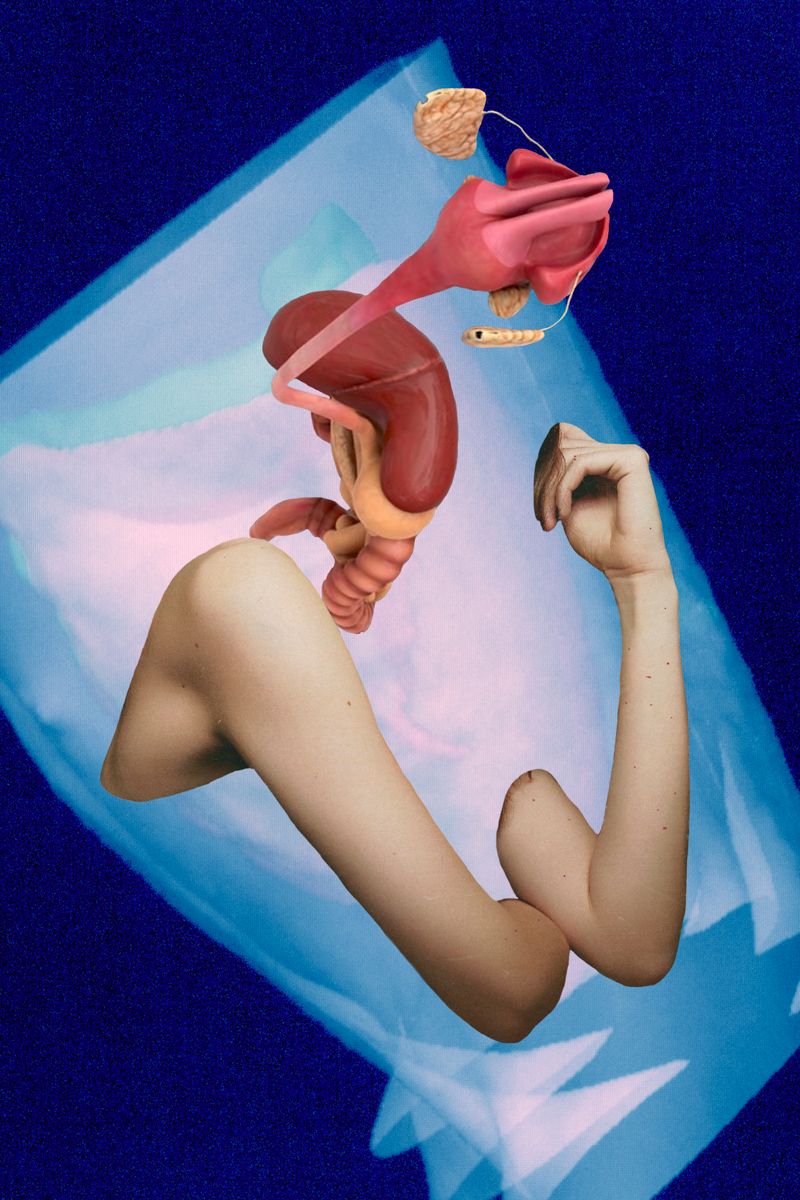

Due to health problems within my family including myself this work derives from a long- term engagement with the human body, its mal-functions and collateral mental issues.

Due to health problems within my family including myself this work derives from a long- term engagement with the human body, its mal-functions and collateral mental issues.

Since the topic being serious and threatening at times, the analysis within the terms of art began to shift from depressing states and strong depictions to more symbolic style of expression alleviating the whole issue.

Combining digital 3-D models of inner organs from the web with scanned cut-outs from magazines, different kind of free associations are made possible. The background consisting of CTs from my check-up enhances the issue of the fragility of our body.

Each image describes a mental state during this period of endurance.